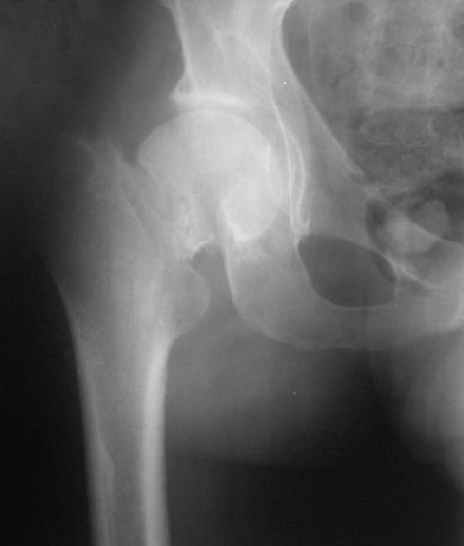

Глубокоуважаемые коллеги,Вчера обратился мужчина 31 г. Травма 2 месяца назад, лечился в одном из городов области. Был не самый тяжелый перелом таза, который проведен консервативно. С ним и связывали невозможность поднять ногу.

Однако на сегодняшнем снимке обнаружился перелом шейки бедра. Больной уже ходитс частичной нагрузкой. Учитывая срок и картину на снимке, что предпринять? У нас предложены варианты 1)не оперировать, 2)закрыто 2 спонгиозных винта, 3)вальгизирующая остеотомия. Эндопротез как-то даже в список включать пока не хочется. Какие есть соображения? Что из перечисленного или что-то другое выбрать и почему? Заранее спасибо.

Dear colleagues,A male 31 years old treated elsewhere after not severe pelvic fracture, was managed non operatively. So the injury looked as a reason of his inability to elevate the leg. However at the recent x-rays the neck fractire was found. The patient already has been walking with partial weight-bearing.Looking at the x-rays and the time since the injury, what is the optimal treatment for now? We discussed 1)leave as is, 2)2 cancellows screws as is, 3)valgus osteotomy. Total hip replacement looks unnecessary yet.What is your opinion? Which option from the listed or something else should be preferred and why?THX in advance.

Варус тут за счет сдвига дистального отломка проксимально. Край шейки на периферическом отломке виден ведь хорошо.

Градусов на 25 больше.

Да как же нет, если головка сползла на 2 см дистальнее и кзади.